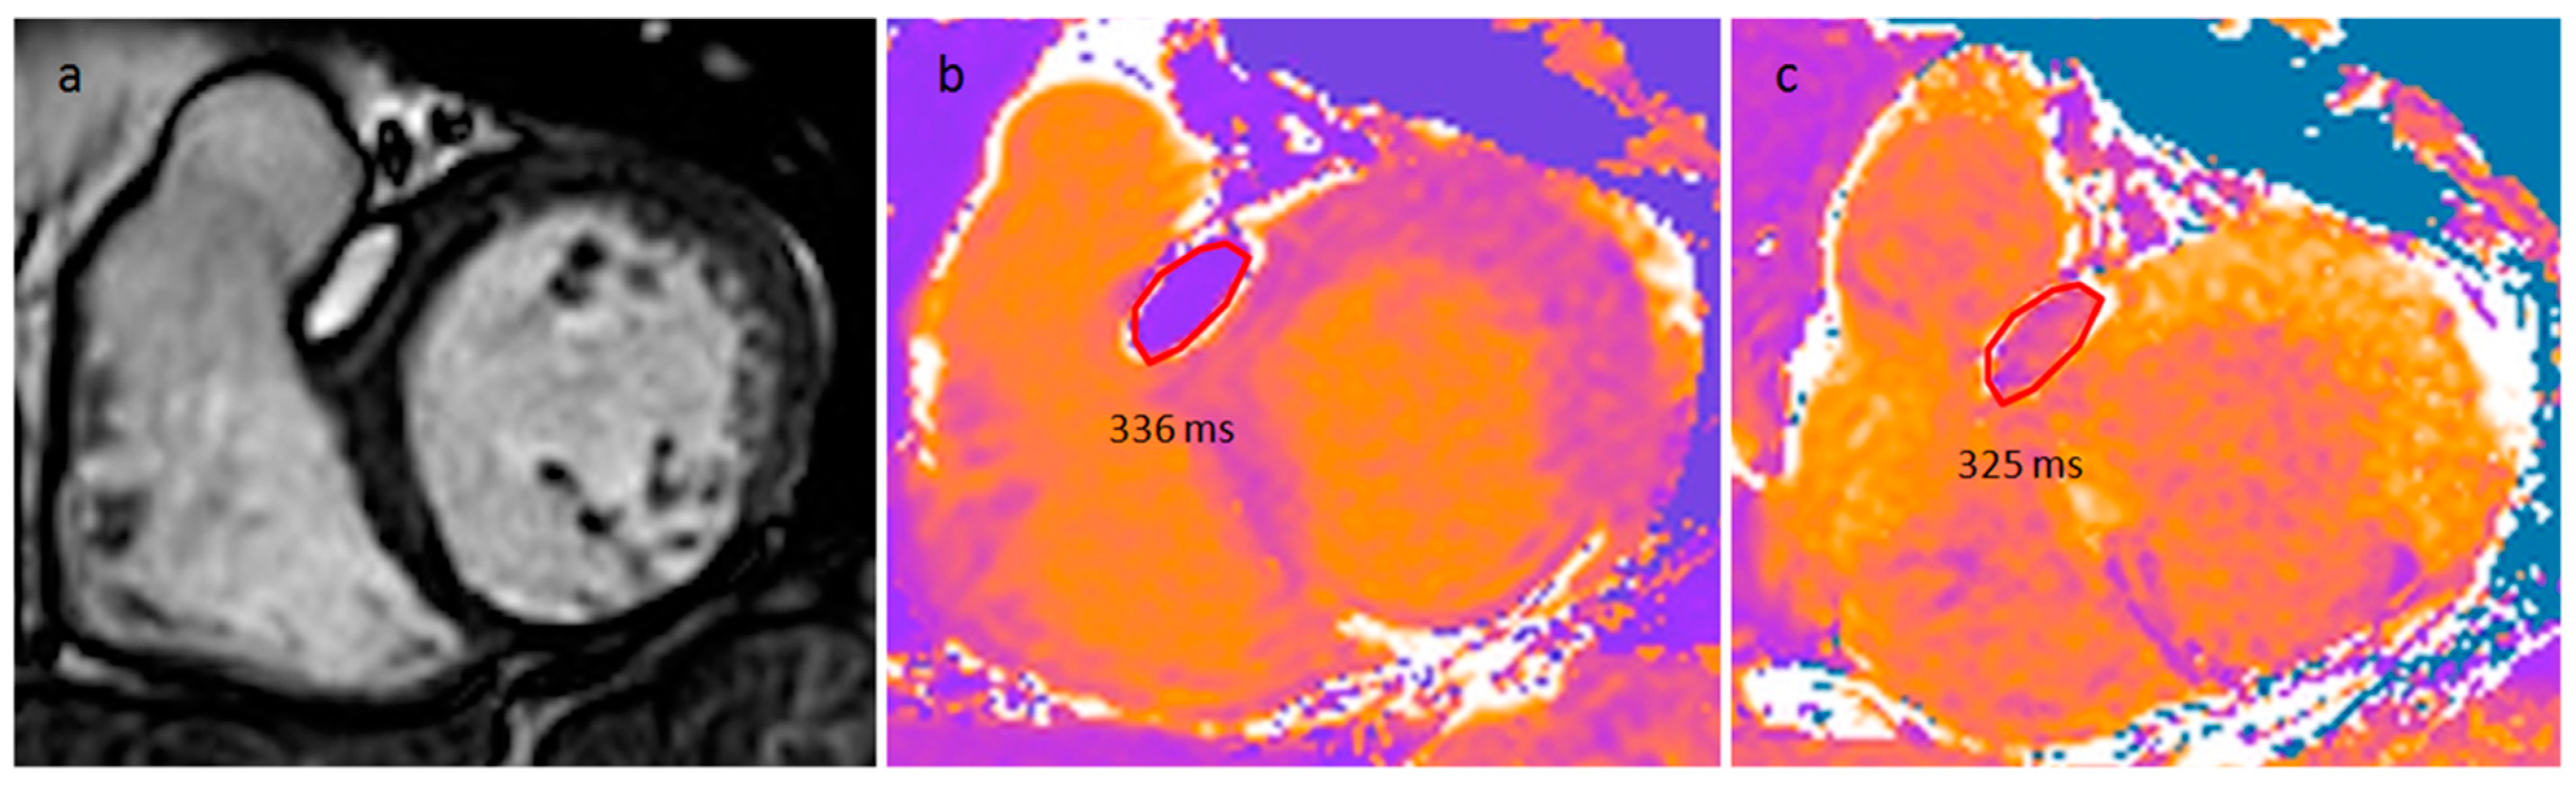

4.1. Myxoma

| Myxoma | Adulthood. Carney complex. | LA | Usually, asymptomatic. Rarely, intracardiac obstruction, embolic events and constitutional symptoms | Mobile mass arising from the IAS | Globular or spherical, with a friable surface and heterogeneous internal echogenicity | Heterogeneous, low attenuation, may be calcified | Isointense T1w, High T2w, heterogeneous LGE |